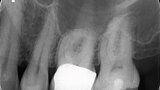

Endodontické ošetření – případová studie